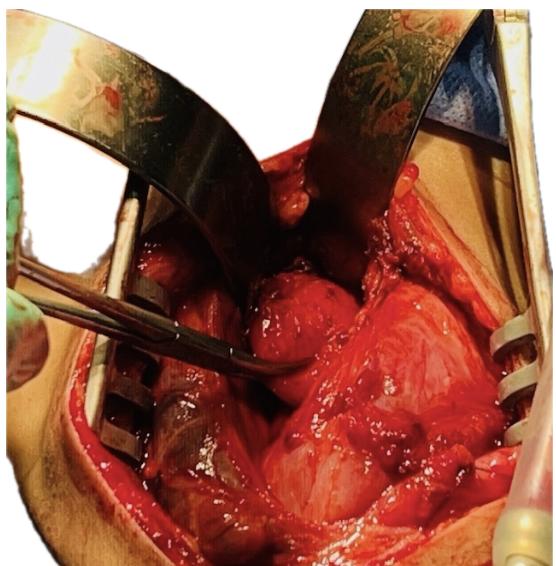

Se practica cervicotomia longitudinal izquierda (borde medial del ECM): se evidencia lesión quística con comunicación a la luz esofágica y cuerpo extraño intraluminal.

Resección completa sin lesión de estructuras adyacentes y esofagorrafia. EVDA de control: paso fácil a cámara gástrica, luz esofágica permeable, sin fugas.

Ubicación en cualquier segmento del esófago 70% en el distal, lesiones bien delimitadas, redondeadas adheridas a la pared , comparten una capa muscular, comunicación parcial generando retención de contraste en la seriadas esofagogástrica, gran simuladores de Divertículos o Pseudoquistes, el Diagnostico es histopatológico.

RESECCIÓN COMPLETA (cervicotomía en lesiones cervicales), manejo de elección con excelentes resultados y baja recurrencia.